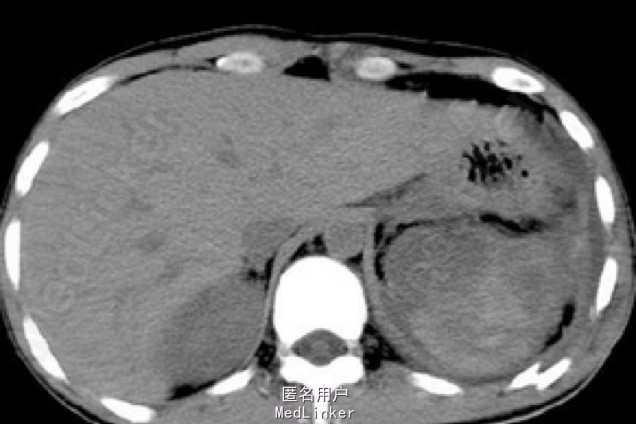

中年男患,于2+天前从高处坠下,全身多处受伤,曾于创伤抢救室就诊,行ct检查提示:颅内出血,肋骨骨折,肺挫伤等,转入某医院治疗,诊断“ 高坠伤,多发伤,颅内出血,肋骨骨折,肺挫伤,鼻骨骨折,上颌骨,右侧眼眶外侧骨折“。半天前出现腹痛,予以腹腔穿刺抽出不凝血,转入我科。下病危,血常规,全腹部ct。 查体:患者神志清醒,头面部肿胀,双眼睑淤紫,瞳孔等大等圆,左瞳直径3MM,右瞳直径3MM,双瞳对光反射灵敏,呼吸道通畅,胸廓正常,胸廓挤压征(+),呼吸正常,已安置闭式引流,双侧肺呼吸音对称,双肺未闻及干湿音,腹部无开放性创伤,全腹无压痛,无反跳痛,四肢无开放性创伤。骨盆无开放性创伤,骨盆挤压征(-),脊柱无叩压痛,耳鼻喉正常,颈部正常,背部无开放性创伤,无其它特殊情况。